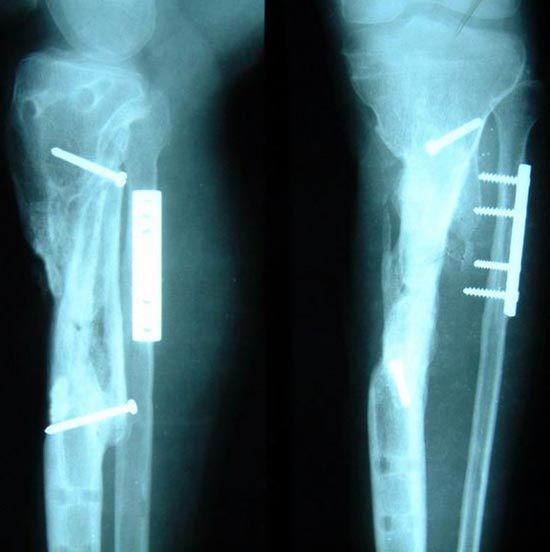

病例二 患者男性,45岁,胫骨上段开放粉碎骨折2年,骨不连

图2-1病例二、患者男性,45岁,胫骨上段开放粉碎骨折2年,骨不连。我们用带锁髓内钉固定骨折端提供支撑力,患者自体骨髓细胞经与松质骨和骨生长因子复合,使没有细胞的植骨材料变成了有细胞的活骨。骨折在9个月后愈合。